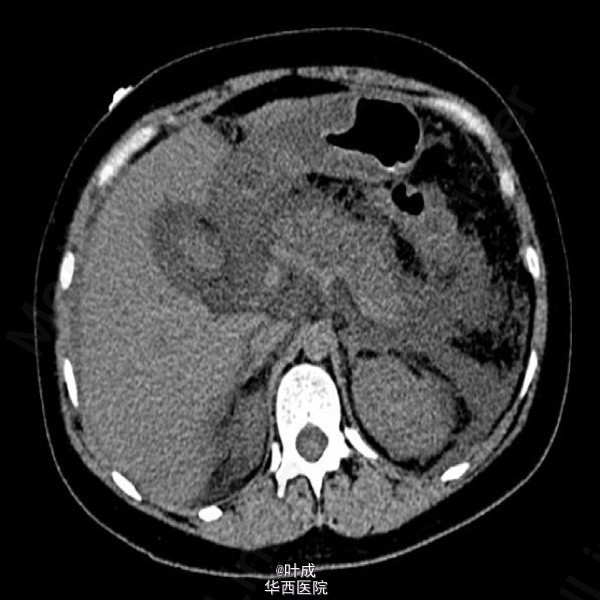

患者女,39岁,因“腹痛2天”入院。患者既往否认胆道疾病病史。入院查体:T:36.5oC,P:130次/分,R:28次/分,BP:135/85mmHg,BMI=25kg/m2。心肺查体无特殊。腹部饱满,全腹肌紧张,上腹压痛,无反跳痛,腹部未触及包块。肝脾肋下未触及。辅助检查:血清淀粉酶 827 IU/L,脂肪酶 720IU/L;血常规:血红蛋白 193g/L,白细胞 8.02*10^9/L,中性粒 80.2%;血甘油三酯 20.33mmol/L,胆固醇 10.80mmol/L;血钙 1.54mmol/L;胸腹部平扫CT示:胰腺肿胀,实质密度不均匀减低,周围脂肪间隙模糊,散在渗出积液影,腹、盆腔、双侧胸腔积液,肺部感染(图2);腹部超声提示脂肪肝,肝内外胆管未见扩张。入院APACHE II评分13分。入院诊断:急性胰腺炎(重度 高脂血症型),肺部感染)。入院后予禁食,控制补液,奥曲肽抑制胰腺分泌,埃索美拉唑抑酸,导泻,加贝酯抑制胰酶,哌拉西林舒巴坦抗感染,维持电解质平衡,补充丙氨酰谷氨酰胺等治疗。患者腹痛症状逐渐缓解,每日出入量大体平衡,但腹胀、气紧症状逐渐加重,沟通后予无创呼吸机辅助通气(中途尝试停用未遂,共使用13天),期间血气分析血氧分压变化见图1(期间存在误采静脉血可能)。患者气紧较前缓解,仍有腹胀,纳差,肛门排期排便可,复查腹部增强CT:胰腺未见明显坏死灶,与之前比较,腹腔积液增多,部分包裹,炎症累及区域脂肪密度降低。双侧胸腔少量积液并双下肺局部肺不张(图3-4);复查甘油三酯 3.63 mmol/L,血清白蛋白>40g/L。治疗上逐步加强肠内营养,予螺内酯利尿,患者腹胀较前有所缓解。